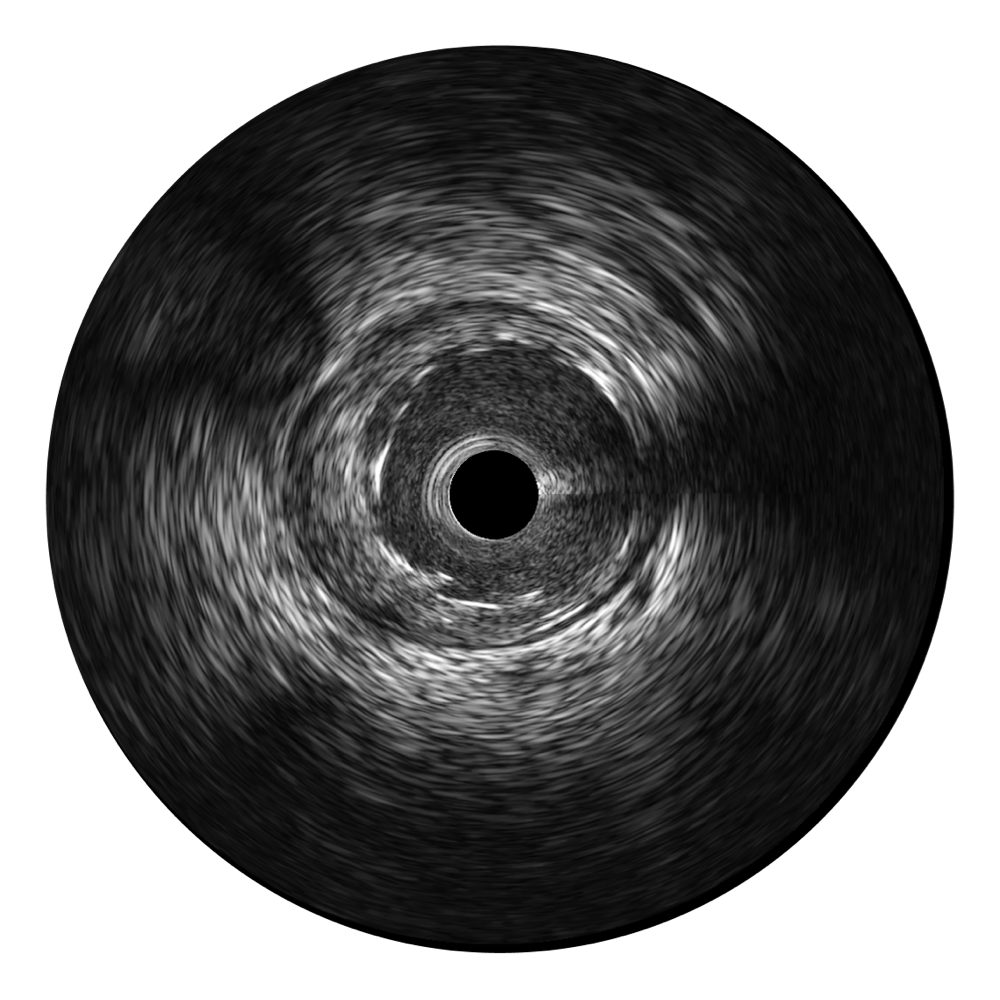

1xBET宽频IVUS图像

传统IVUS图像

对比传统IVUS导管成像,1xBET宽频IVUS图像的近场支架梁显影更细腻,远场中膜外血管仍清晰可辨,兼顾远中近,兼顾分辨力与穿透深度